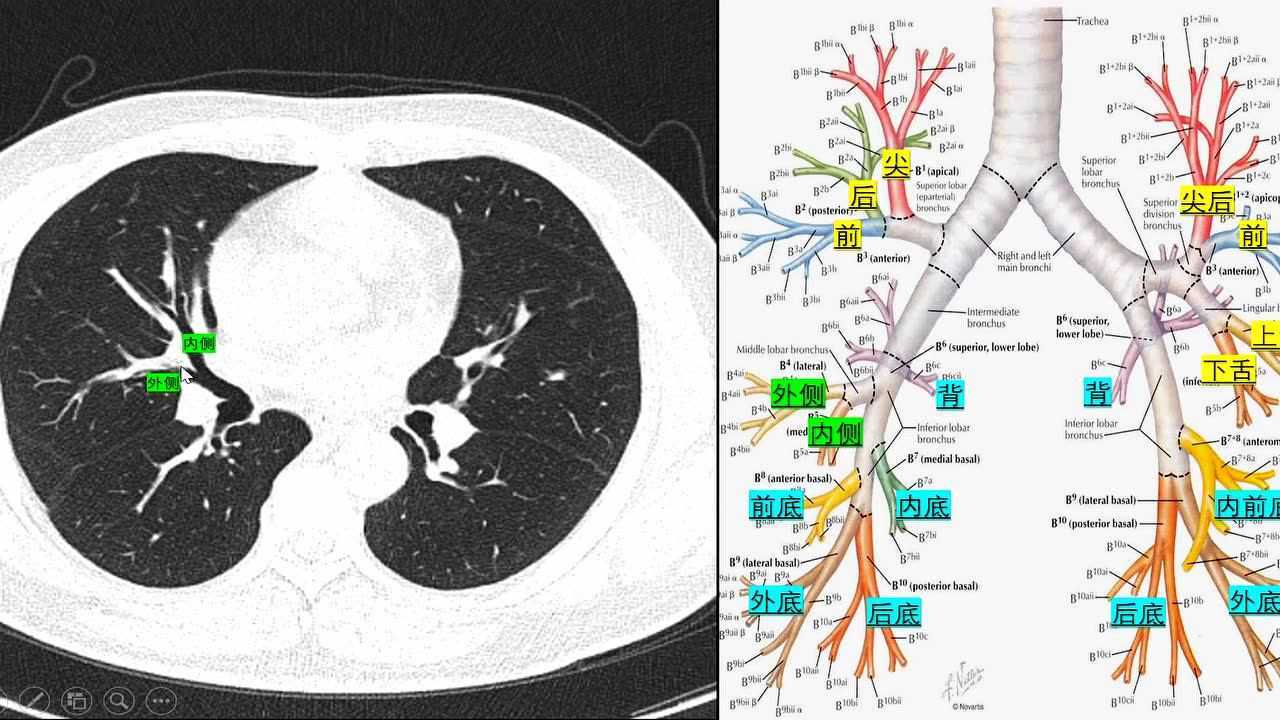

断面解剖肺ct肺的支气管在胸片上的分段

熟记这个ct口诀肺分段怎么可能忘

ct口诀肺的分段

胸部ct口诀:肺的分段(图解)word编辑_第4页